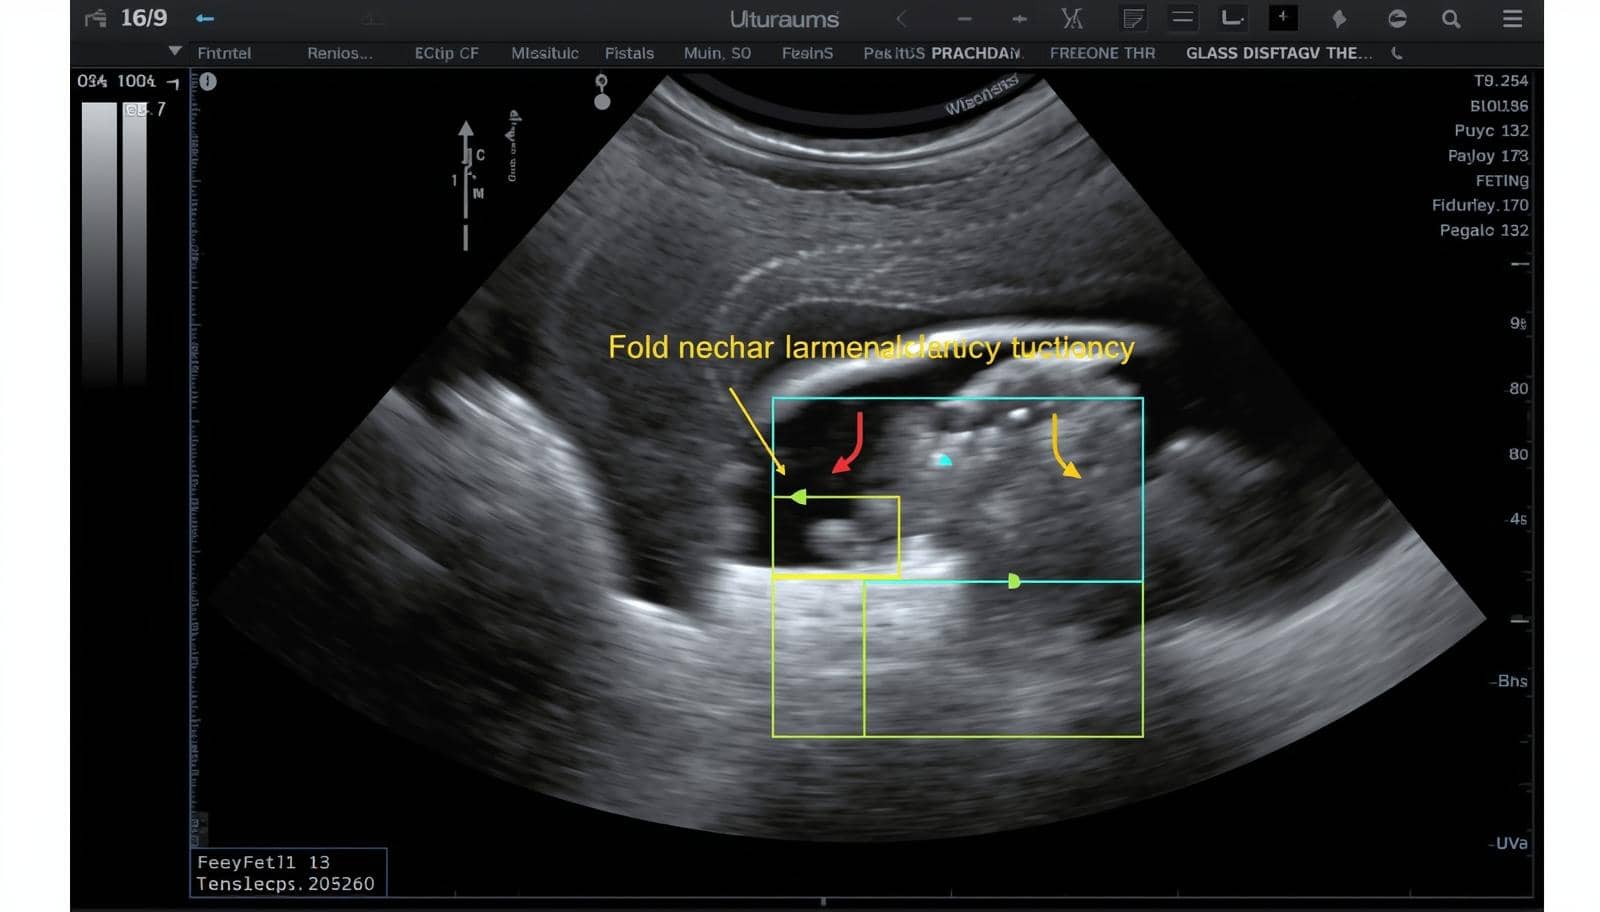

photo d'une échographie montrant un foetus avec trisomie 21 : Emmanuel-SOS-Adoption

Le dépistage prénatal de la trisomie 21 a considérablement évolué ces dernières décennies. En France, un dépistage combiné est proposé systématiquement au premier trimestre de grossesse, associant échographie (mesure de la clarté nucale) et marqueurs sériques maternels.